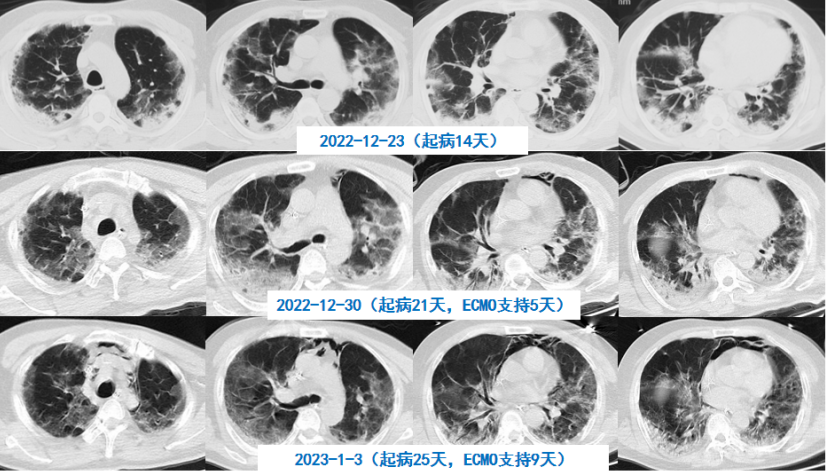

58岁男性患者,糖尿病病史,由于病情较重,2022年12月23日(起病14 d)胸部CT如下图所示。

图片

患者2022年12月23日胸部CT

于起病16 d行气管插管机械通气,但氧合仍难以维持,12月25日启动ECMO。

予地塞米松10 mg qd,同时予巴瑞替和托珠单抗治疗,患者CRP明显下降。1月4日因患者循环不稳,担心管路相关血流感染引起感染性休克,撤离ECMO。在ECMO期间,患者临床指标和氧合均得到明显改善,影像学明显吸收。

患者胸部CT变化情况